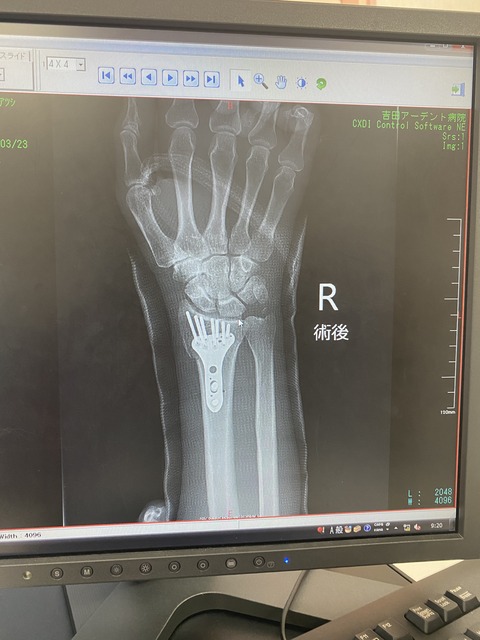

最後におかんの採血なんやけど、右腕はギブスであかんし